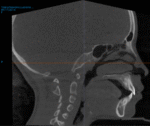

- Relación con postura y crecimiento

- Posición mandibular

- Colapso posterior de lengua

- Relación con columna cervical

Aquí conectas perfecto con:

- SNA

- postura

- desarrollo craneofacial

- Predicción de riesgo respiratorio

- Áreas críticas estrechas

- Patrón de vía aérea colapsable

- ATM (articulación temporomandibular)

- Cóndilo

- Fosa glenoidea

- Asimetrías

👉 Muy útil en pacientes con dolor o disfunción